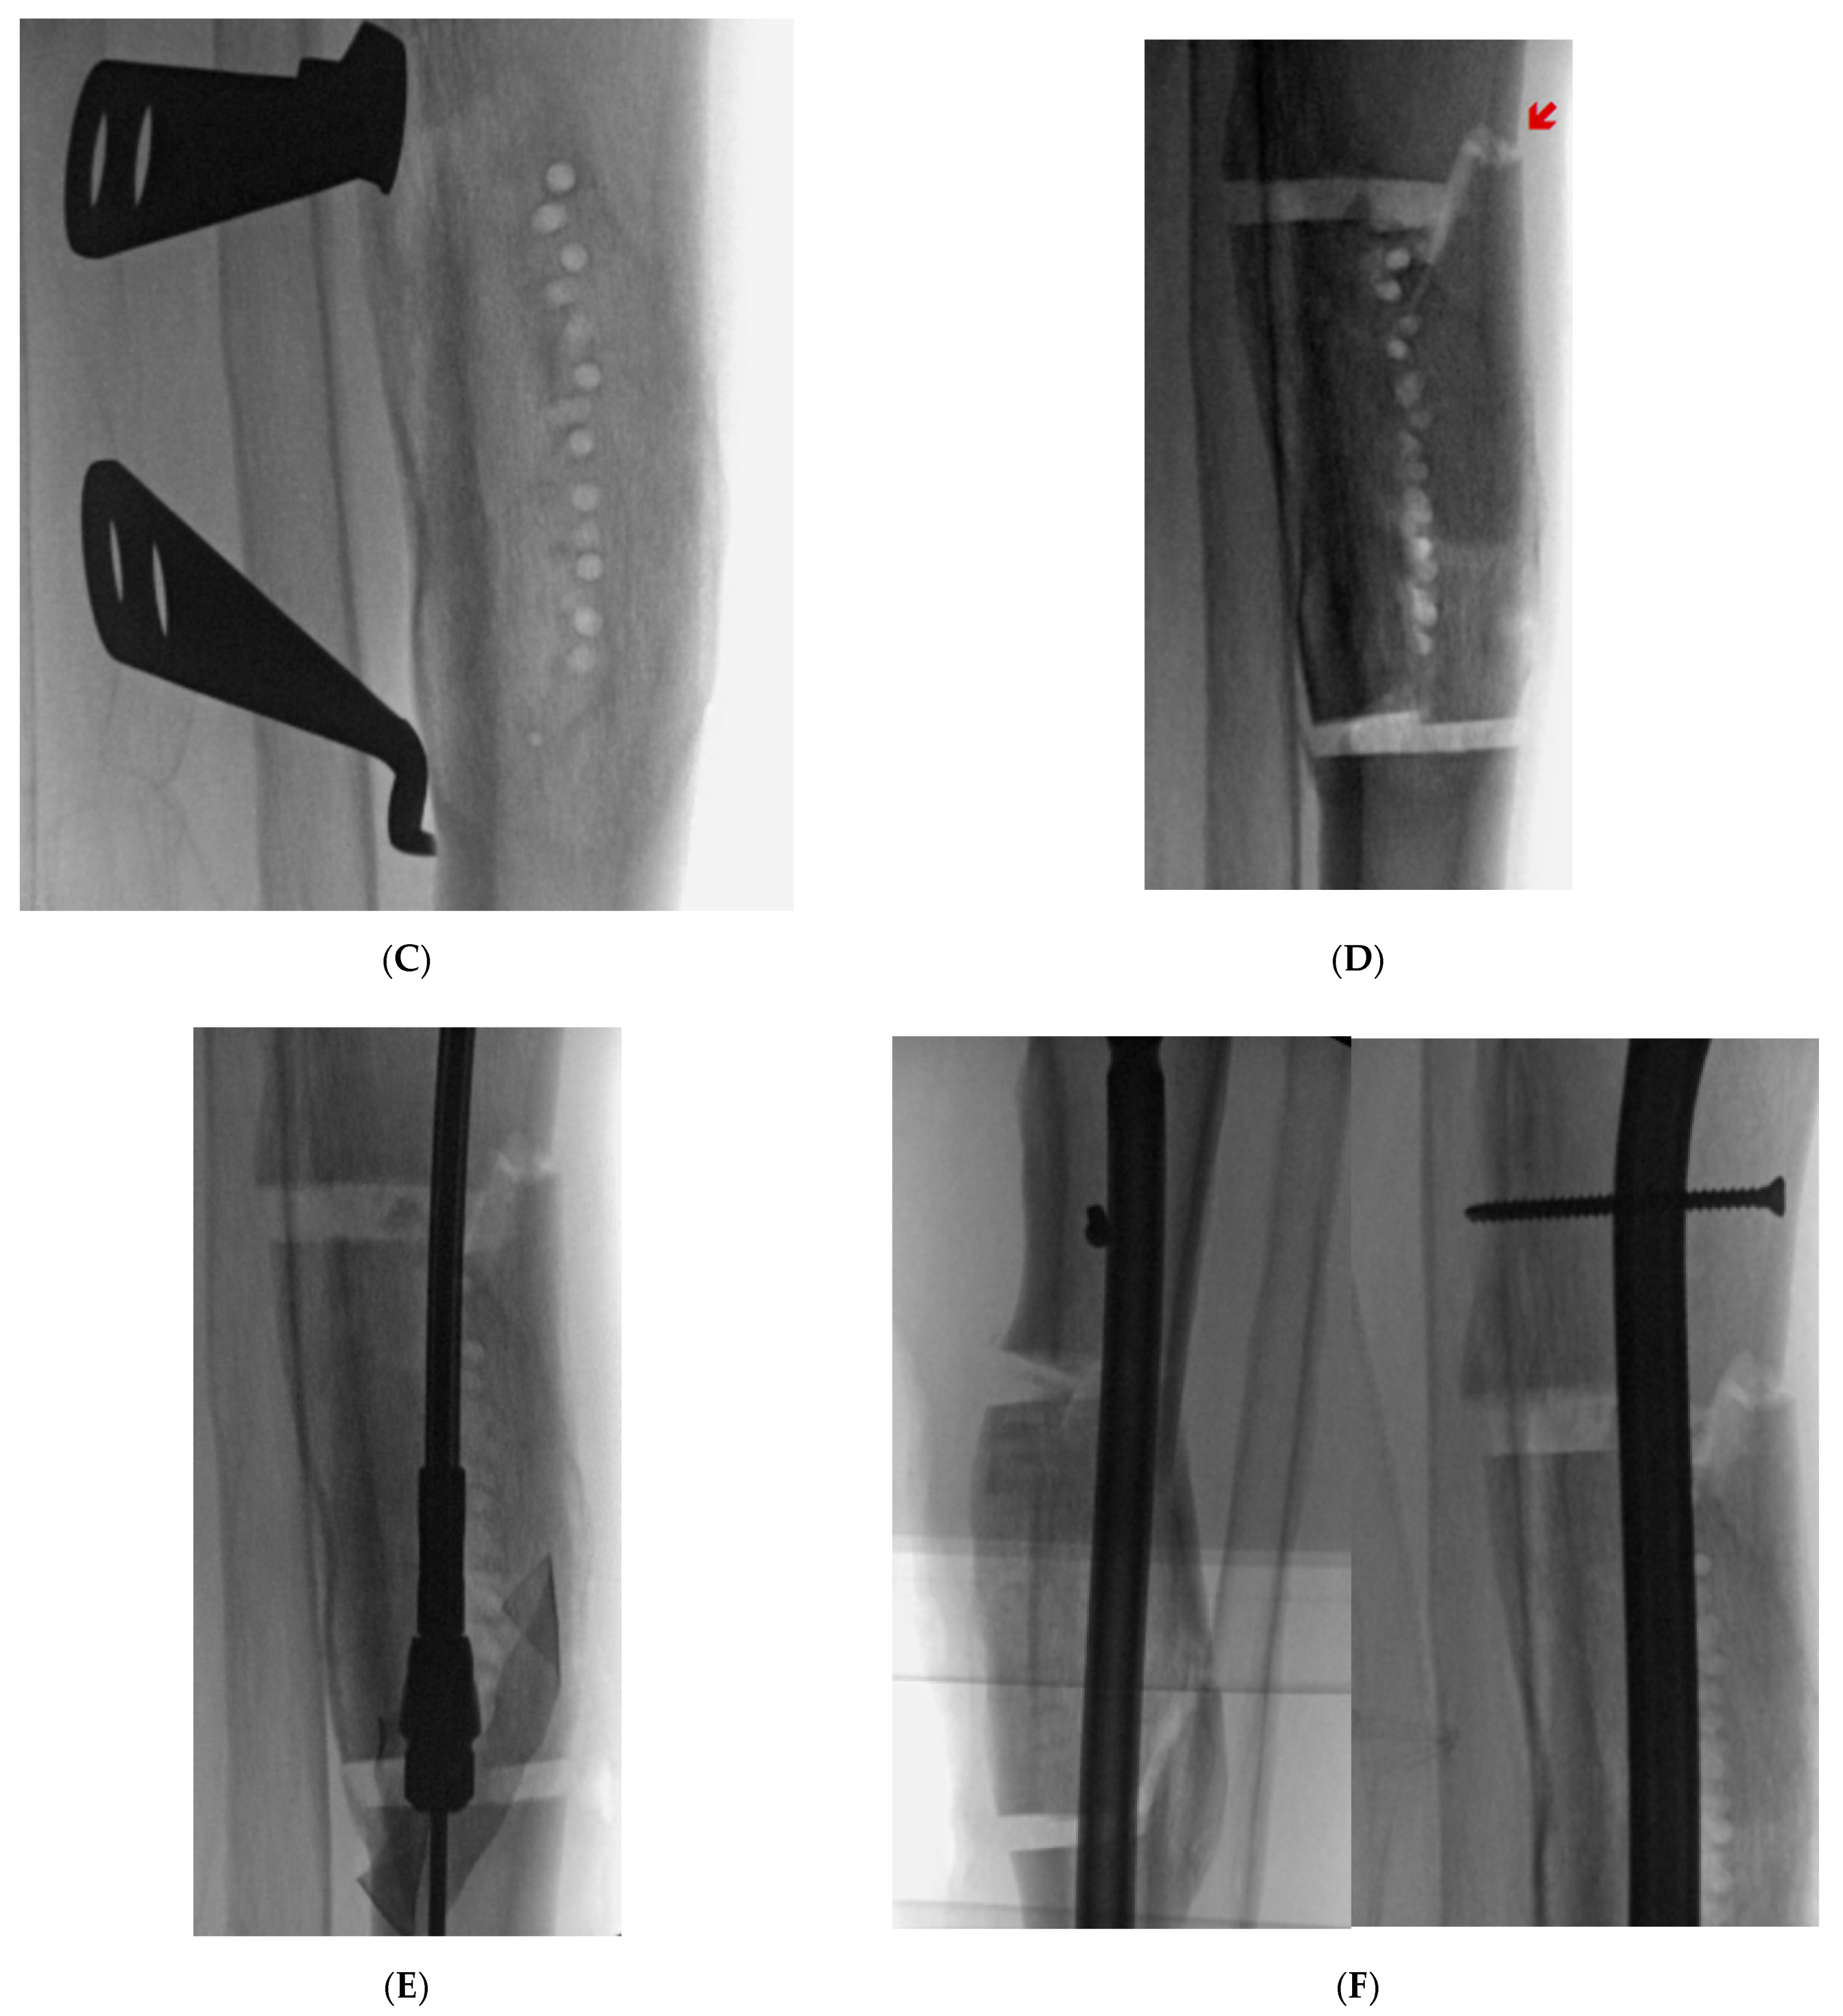

9.4. Case 4

A middle-aged female was treated at an outside facility for distal quarter tibial shaft. She was treated with open reduction internal fixation through a posteromedial approach. She developed a deep infection warranting irrigation and debridement with plate removal. She subsequently developed a stiff varus internal rotation non-union of her tibia and a segmental fibular shaft non-union/malunion. She reported severe pain with ambulation and body dissatisfaction with her tibial deformity. Her past medical history was significant hypertension and diabetes. She was referred to our facility. Her distal valgus deformity measured 26°. She underwent a clamshell osteotomy to correct the tibial diaphyseal malunion and bypass the stiff non-union (Figure 7). A fibular osteotomy was required for correction. The clamshell allowed for placement of an intramedullary rod through the canal at the non-union site, which was very limited in diameter secondary to her failed healing and deformity. An anterolateral approach was used to perform the clamshell osteotomy. She healed her osteotomy uneventfully without any complications.

Figure 7. (A): AP and lateral XR demonstration varus non-union deformity with segmental fibular fracture. (B): Intraoperative fluro view with threaded k-wire at proximal and distal aspect of malunited segment. A core reamer is being used to create the sequential bicortical drill holes. A core reamer can be used if the malunited segment is significantly larger than a 3.5 drill bit. (C): Note the lamina spreaders being utilized to open the osteotomized clamshell segment. (D): Medial universal distractor being utilized to assist with deformity correction. The distractor can be left in place during the nailing procedure. (E): AP and lateral 3-month postoperative radiographs demonstrating healed clamshell and fibular osteotomies.